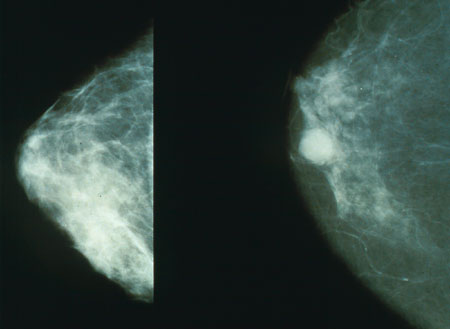

Cáncer de mama . Mamografía.